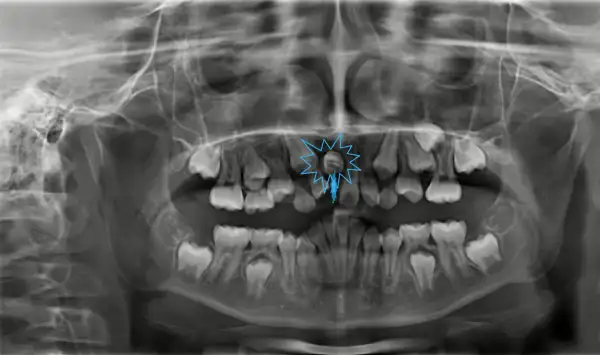

Hàm răng của con người được đánh số hoặc phân loại theo vị trí và chức năng. Thông thường, răng được chia thành các nhóm chính như răng cửa, răng nanh, răng cối nhỏ và răng cối lớn. Răng số 8 là răng khôn. Việc xác định chính xác răng vĩnh viễn là răng nào và số thứ tự của chúng giúp ta hiểu rõ hơn về cấu trúc hàm răng.